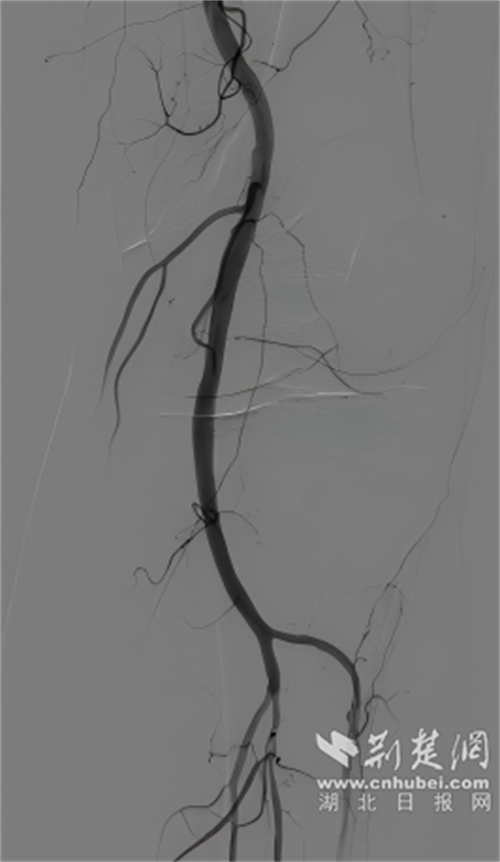

球囊扩张术后。通讯员 供图

介入治疗后。通讯员 供图